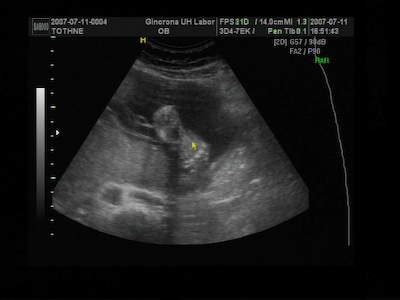

A 4D-s vizsgálaton nekem azt mondták ,hogy 5 nappal kisebb a baba, de ez még belefér ezért nem változtattak semmin , és lehet,hogy még előbb is kibújhat.